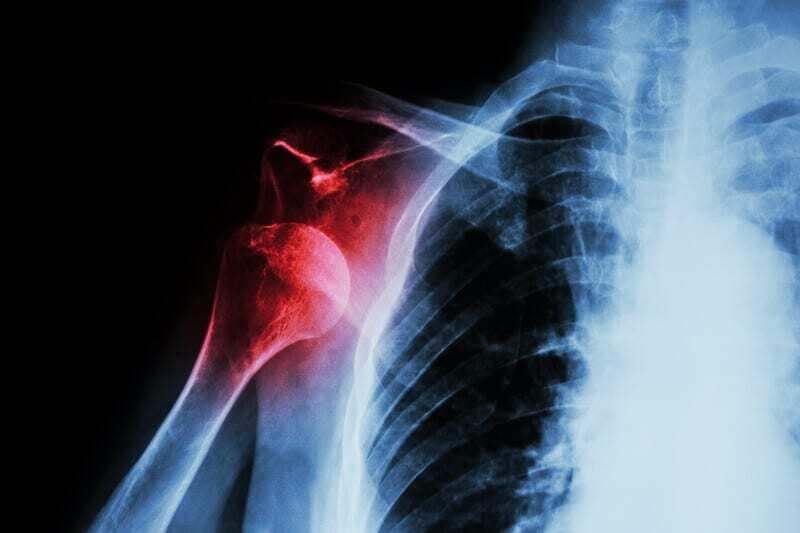

The shoulder is a special joint as it is really a combination of several joints—combined in such a way by an intricate arrangement of muscles and tendons—that provides the arm a wide range of motion, flexibility and stability. The rotator cuff is a group of four shoulder muscles that surround the top of the upper arm bone, (the humerus), and holds it in the shoulder joint. These muscles are responsible for moving the arm in various directions, and unlike the massive deltoid muscle of the upper arm, are smaller and generally more vulnerable to injury. The four muscles and tendons of the rotator cuff are the supraspinatus, infraspinatus, teres minor, and subscapularis. It is the supraspinatus that is most commonly inflamed or torn.

The supraspinatus, and the rest of the shoulder, because it is built and expected to allow a remarkable array of motion, frequently is subjected to the injuries listed below, causing problems of instability or impingement of soft tissue and pain. The pain may be constant, or may occur only when the shoulder is moved. In any case, severe shoulder pain that persists more than a few days should be diagnosed and treated as necessary.

Chronic shoulder instability syndrome results from a loosening of the connective tissue caused by trauma such as dislocations, subluxations (partial dislocations of the shoulder), and from less detectable micro-traumas caused by repetitive strain, or from congenitally loose shoulder joints. Recurrent pain or tenderness in the shoulder joint and weakness in the arm are two of the more common symptoms, but severe examples include patients whose shoulders pop in and out of joint. Frequent shoulder dislocations stretch the brachial plexus, the nerves that run from the neck down the arm. This process can cause permanent nerve damage, pain, and loss of use of the arm.

Within the shoulder are its three main joints. Most dislocations or subluxations occur in the glenohumeral joint, the ball and socket joint. Lesser or more rare dislocations occur at the acromioclavicular or AC joint and sternoclavicular joint, the SC joint.